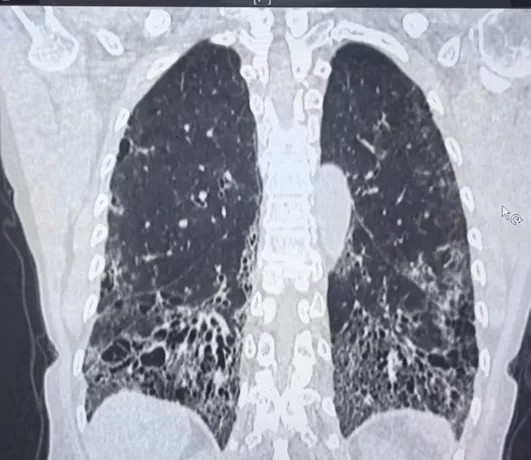

呼吸科:通过高分辨率CT(HRCT)观察肺部纤维化或炎症痕迹,判断病变范围;

影像科:像“肺部侦探”,通过CT图像细微差别区分炎症、纤维化或血管问题;

擅长:特发性肺纤维化、结缔组织病相关肺间质病变的肺病高分辨率CT特征解析与鉴别诊断;熟练应用人工智能辅助影像分析,提升早期肺纤维化检出率及预后预测精度。